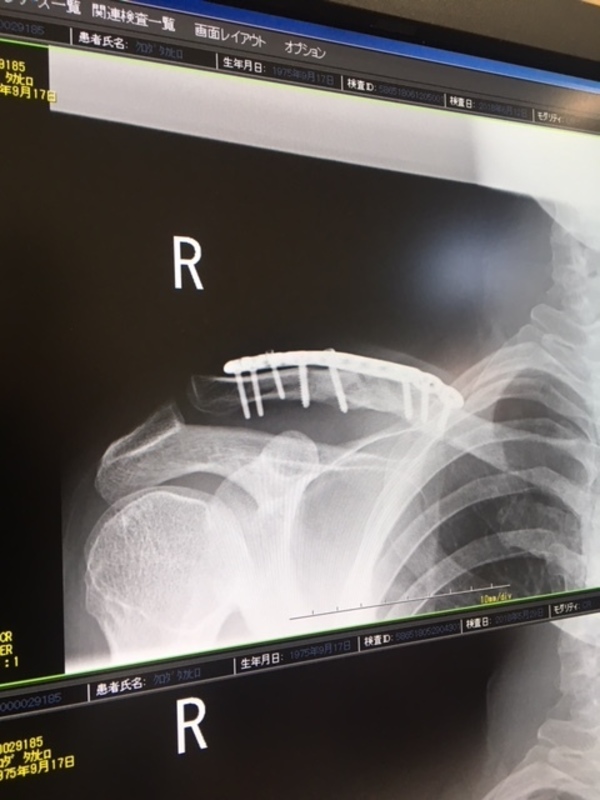

ほぼフツウなんです。

もうええねんやで。先生なんもゆ~てくれません。今時のプレートすごいんですよ~。ぐらいしかいいません。でも分かるんです。多分ひっついてます。見えるんです。だって鎖骨だもの。

まあ7月ぐらいからでしょ~か。乗るのは。 えへへ。